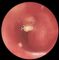

Туберкулема легких представляет собой плотный обычно округлый казеозный очаг диаметром более 1 см, имеющий выраженную капсулу (рис. 14). Более чем у половины больных туберкулема является исходом других форм туберкулеза легких. Обычно ей предшествует очаговый туберкулез, реже она образуется на фоне инфильтративного процесса (в результате рассасывания перифокального воспаления и осумкования казеозных масс) или вследствие закупорки дренирующего бронха у больных кавернозным туберкулезом легких.

Клиническая картина при туберкулеме легкого определяется фазой туберкулезного процесса. Вне обострения субъективные симптомы, физикальные изменения, патологические сдвиги в крови и бактериовыделение отсутствуют. Туберкулема легкого в этом случае может быть выявлена только при рентгенологическом исследовании, часто ее обнаруживают при профилактическом флюорографическом обследовании. На рентгенограмме туберкулема легкого имеет вид округлой, четко отграниченной тени. Тень солитарной туберкулемы может быть однородной, неоднородной (с более плотными включениями и кальцинатами). Тень конгломератной туберкулемы состоит из нескольких фокусов. В окружающей легочной ткани часто определяются очаги туберкулезного воспаления, фиброз, во внутригрудных лимфатических узлах — кальцинаты. В 60—70% случаев, чаще при небольших туберкулемах (до 2 см в диаметре) у больных, не страдающих серьезными сопутствующими болезнями (сахарным диабетом, язвенной болезнью и др.), процесс может быть стационарным на протяжении многих месяцев и даже лет. Многолетняя стабильность процесса и отсутствие клинико-рентгенологических и лабораторных признаков его активности не исключают существования вегетирующих микобактерий туберкулеза в казеозных массах туберкулемы, а также морфологических признаков активности специфического процесса в ее капсуле, а следовательно, и возможности его реактивации (которая отмечается приблизительно у 10% больных с длительной стабилизацией процесса). Поэтому даже при отсутствии обострений на протяжении 5 и более лет следует с большой осторожностью говорить об излечении, его считают возможным только у больных с туберкулемой, диаметр которой не превышает 1,5—2 см.